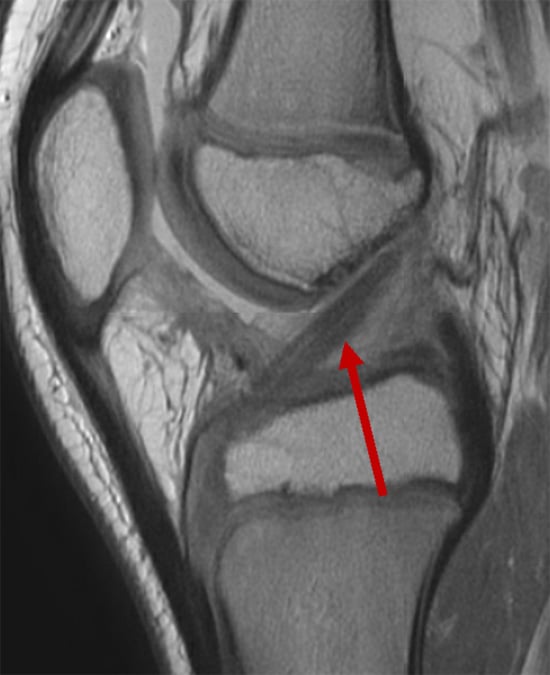

MRI showing a reconstructed anterior cruciate ligament.